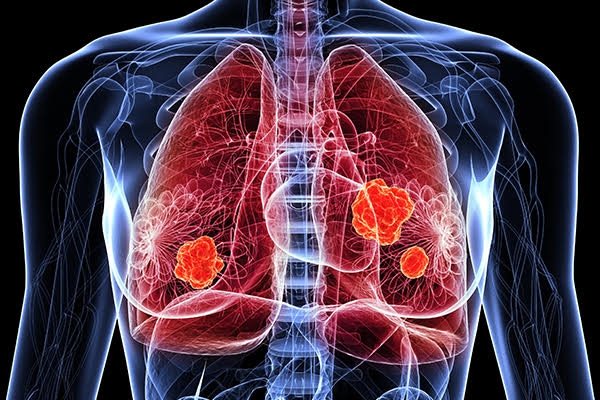

폐암은 원발성 폐암을 말하며 원발성 폐암은 폐에서 기원하는 악성 종양을 말한다. 폐로 전이된 암은 폐로 전이된 것으로 분류되며, 폐암이라기 보다는 기원 장기로 전이된 것으로 분류된다. 폐암은 조직학적 유형에 따라 크게 소세포폐암과 비소세포폐암으로 분류된다.

이러한 폐암의 원인으로 인해 폐암으로 진단되기 전에 폐암 초기증상을 조기에 발견하면 다른 장기로의 전이나 진행성 폐암으로의 진행을 어느 정도 지연시키거나 적절하게 치료할 수 있지만 일반적으로 폐암의 초기 단계는 특별한 징후나 증상이 없으므로 조기에 발견하는 경우는 극히 드뭅니다.

뇌는 또한 폐암이 전이되는 장소 중 하나입니다. 폐암의 증상으로는 두통, 구토, 드물게 발작이 있습니다. 다른 신체 증상으로는 악액질, 구토, 가스, 식욕 부진 및 체중 감소가 있습니다. 그 중 악액질은 이른바 둠스데이로 혈우병, 결핵, 암 등 악성질환이 말기에 접어들면 나타나는 고도로 쇠약해진 상태를 말한다. 살이 빠지면 무기력해지고 발, 눈꺼풀 등 다양한 부위에 부종이 생길 수 있으며 심한 빈혈은 피부가 뿌옇고 노랗게 변할 수 있다.